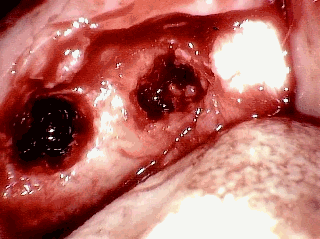

These next two images are my own surgery pictures. The first picture is with the gum retracted. You can see small holes in the bone. That is diseased bone. The second picture is with top cut off the bone. You can see there is just a giant hole that extends back into my jaw. I was actually awake during the surgery, and made sure my dentist took those pictures, specifically for this website.

These next two pictures are from the same dentist. They are the typical cavitations formed after the extraction of teeth. The text from the website reads:

"Bone exposed on flap retraction. Note the open defect in the bone some 20+ years after the extractions. The defect was directly under the fibrous attachment. "